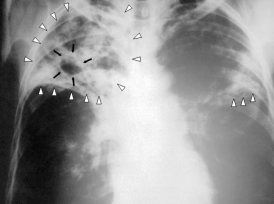

Впервые за многие годы на улицах Лондона появились туберкулезные двухэтажные автобусы, оснащенные рентгеном, в них можно бесплатно пройти обследование. Такие автобусы ездили в Европе и в США в 50-х годах. Они исчезли после того, как заболеваемость резко упала. Но в Лондоне, как говорит руководитель одной из таких лабораторий на колесах доктор Элитер Стори, туберкулез стал большой проблемой. Известно, что 95 процентов ежегодной смертности от туберкулеза миллиона человек приходится на развивающиеся страны.